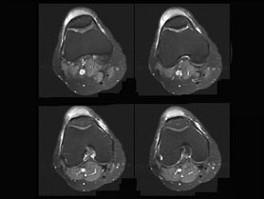

问题 男, 20岁,膝关节部前方肿痛,轻度发红、发热,结合MRI图像,最可能的诊断是 ( )

选项 A、半月板撕裂 B、髌前囊炎 C、髌骨挫伤 D、膝关节炎 E、未见异常

答案 B